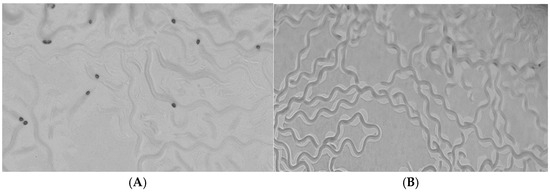

2D Monolayer In Vitro Nanotoxicity

In Vitro Nanotoxicity Using 3D Spheroid Culture (Multicellular Tumor Spheroids)